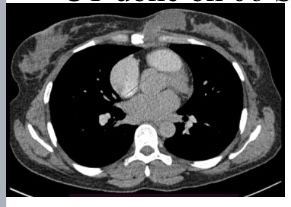

Mammogram Left MLO view shows a circumscribed high-density round to oval lesion in the upper quadrant near the axillary tail. Another partially visible high-density lesion is seen in the lower inner quadrant posterior third of the breast ( retroglandular zone) near the chest wall. Corroborative USG of the upper outer quadrant lesion revealed a hypoechoic round to oval lesion with microlobulated margins while the lower inner quadrant lesion revealed an anechoic collection with fine internal echoes reaching up to the chest wall with areas of bone erosion of the sternum. CT was done to see the extent of collection and other lesions which showed a hypodense collection in the chest wall near the sternum with areas of bone erosion and a hypodense round to oval lesion near the axillary tail. PET CT was done for academic purposes which showed uptake from the chest wall lesion near the sternum with no uptake in the hypodense collection. Biopsy was done from both the upper outer quadrant and chest wall lesion.